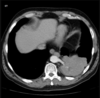

2 anos, masculino

Cisto de duplicação esofágico

Predleção por meninos; diagnosticados na infância

Em geral assintomáticos; podem provocar estridor

Mais comuns no esôfago distal; geralmente não comunicam com a luz do esôfago;

TC: Cisto com densidade de líquido, margens bem definidas que podem realçar com contraste; podem complicar com hemorragia, infecção: nível liquido, espessamento parietal.